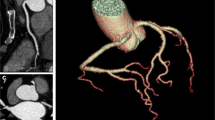

The image noise, defined as the standard deviation of pixel attenuation values in a visually homogeneous region of interest (ROI), was measured in the most cranial part of the liver parenchyma in each scan, as illustrated in Fig. 1. Next, image noise was fitted to multiple patient-specific parameters (P) which were considered easy applicable in daily use; body weight, BMI and MPL, to determine a possible increase in image noise for heavier patients (see Table 1).

Fig. 1

figure 1

Example of axial slices of two CCTA scans, including the regions of interests, demonstrating the increase in image noise and decrease in image quality in heavier patients. Both scans are from female patients. a A lean patient of 69 kg, BMI 24.4 kg/m2 and MPL 41.1 kg/m and b a more obese patient of 89 kg, BMI 39.6 kg/m2 and MPL 59.3 kg/m. Images were acquired using the same tube voltage of 120 kV and tube current of 400 mA. The measured image noise for the lean patient is 47 HU and for the more obese patient 87 HU